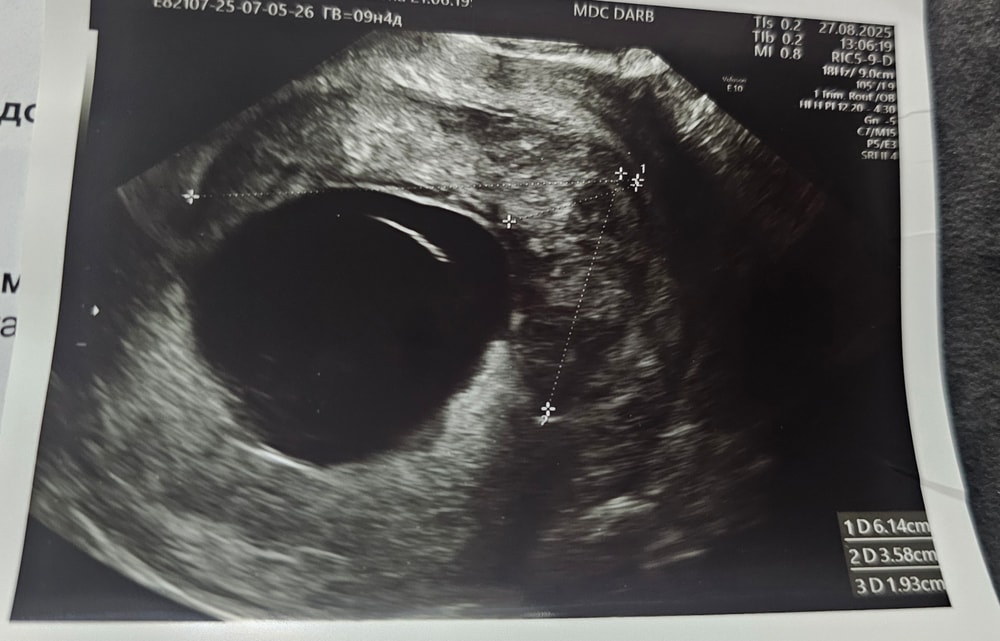

Ретрохориальная гематома больших размеров.

Изображение Изображение